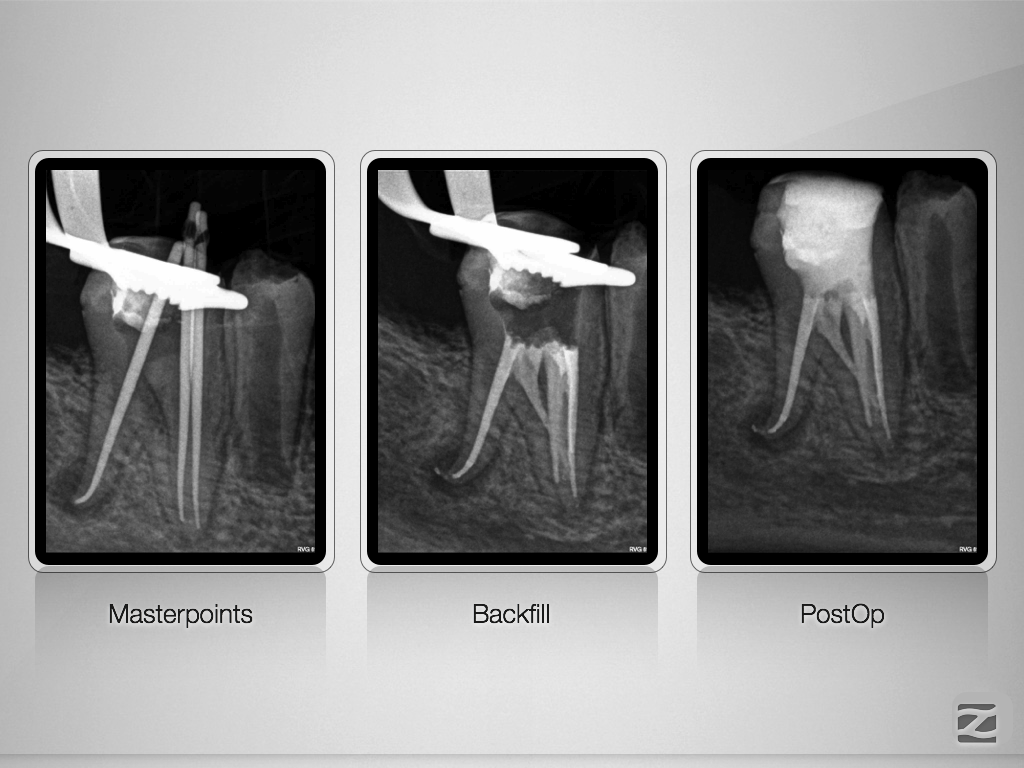

46D.010

Doppeltes C